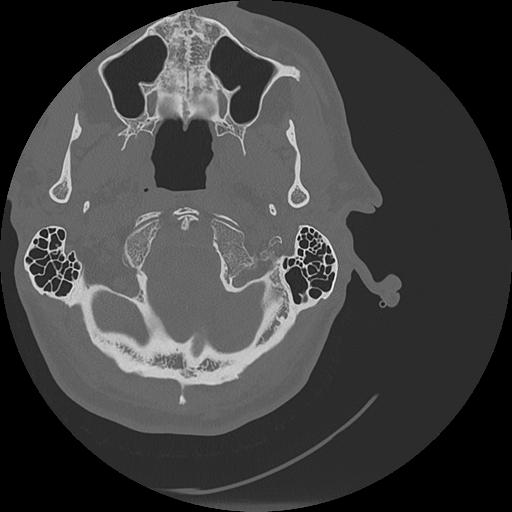

7 HUESO,,Vol,0.5,HUESO,,